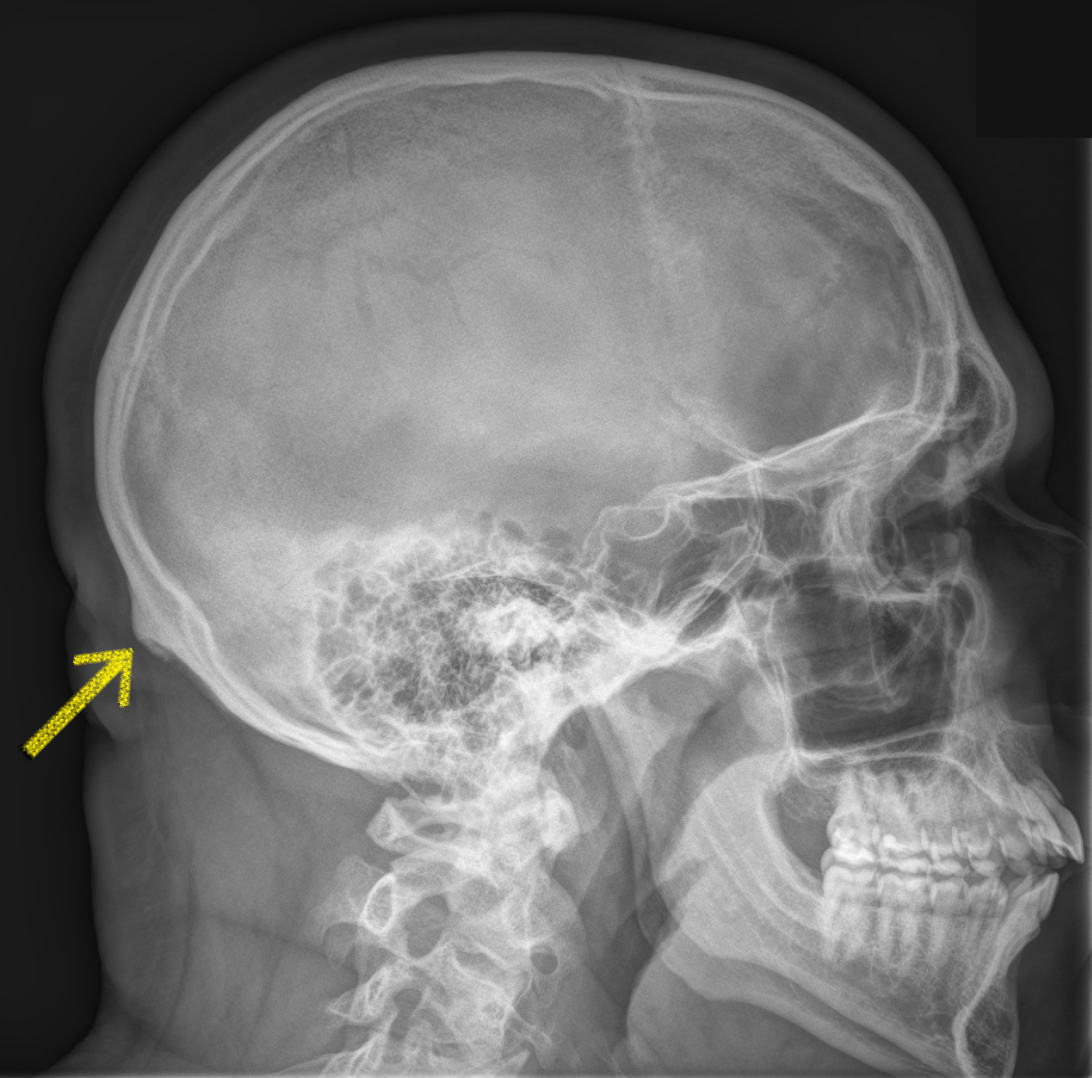

Анатомия мозга: Рентгеновские снимки для презентаций